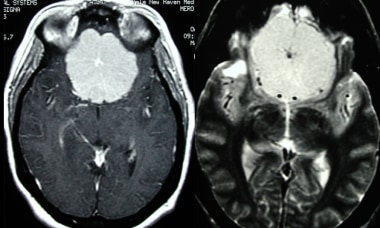

无对比和有对比的横轴位CT显示在这种强烈增强的脑膜瘤内有轮辐状图案。虽然这种模式通常在血管造影中看到,但也可以在横断面成像中注意到。

随后的核磁共振成像显示先前的计算机断层扫描具有以下序列:钆注射后的轴向T1和轴向T2序列。这再次显示了一个较大的中线额骨脑膜瘤,呈轮辐状。